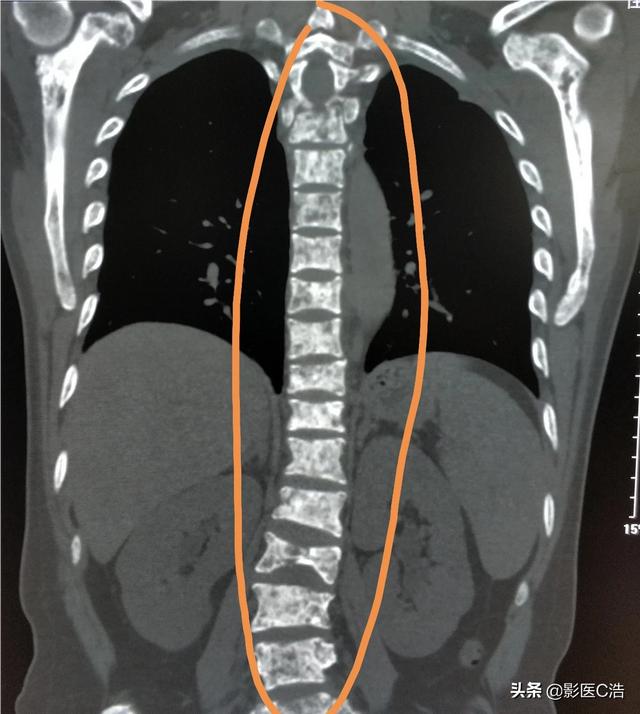

Quel type de douleur doit alerter sur la présence de métastases osseuses ? Les métastases osseuses sont une manifestation fréquente des tumeurs malignes à un stade avancé. La tumeur primaire présente dans d'autres parties du corps se métastase dans les os par les voies sanguines et lymphatiques, formant ainsi des métastases osseuses. Les métastases osseuses signifient que le tissu osseux normal a été détruit et remplacé par du tissu tumoral. Les métastases osseuses peuvent être classées en trois types selon la spécificité de la lésion : le type ostéolytique, le type ostéogénique et le type mixte. Les sites courants de métastases osseuses sont l'os de la diaphyse moyenne (colonne vertébrale et bassin), les côtes et la métaphyse inférieure, l'os de la diaphyse moyenne étant le plus courant, ce qui est lié aux caractéristiques de l'apport sanguin dans cette zone. Comme le montre le cercle ci-dessous, les métastases osseuses sont multiples et la colonne vertébrale est en mauvais état.

Montrant un cancer avec métastases osseuses survenant dans la colonne vertébrale thoracique